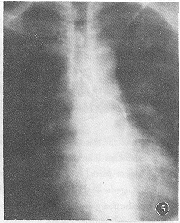

實驗室檢查無特異性結果,腦脊液檢查結果多,在正常範圍,偶見蛋白總量增多。做X線、造影、CT及MRI等檢查。本病徵的治療應針對病因,可使用抗凝劑、抗感染等療法、對症治療和促進功能恢復的理療、中藥及針灸治療等有較好的治療效果。一般病例經綜合治療後,括約肌功能首先恢復正常、其次是感覺障礙的消失,運動功能的恢復最遲。病程越長、恢復越差。